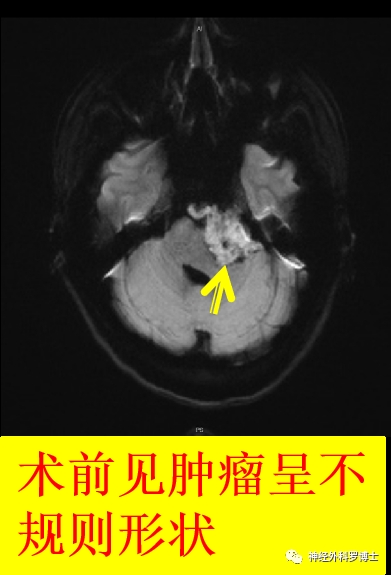

术前磁共振弥散

术后磁共振弥散示肿瘤切除较完全